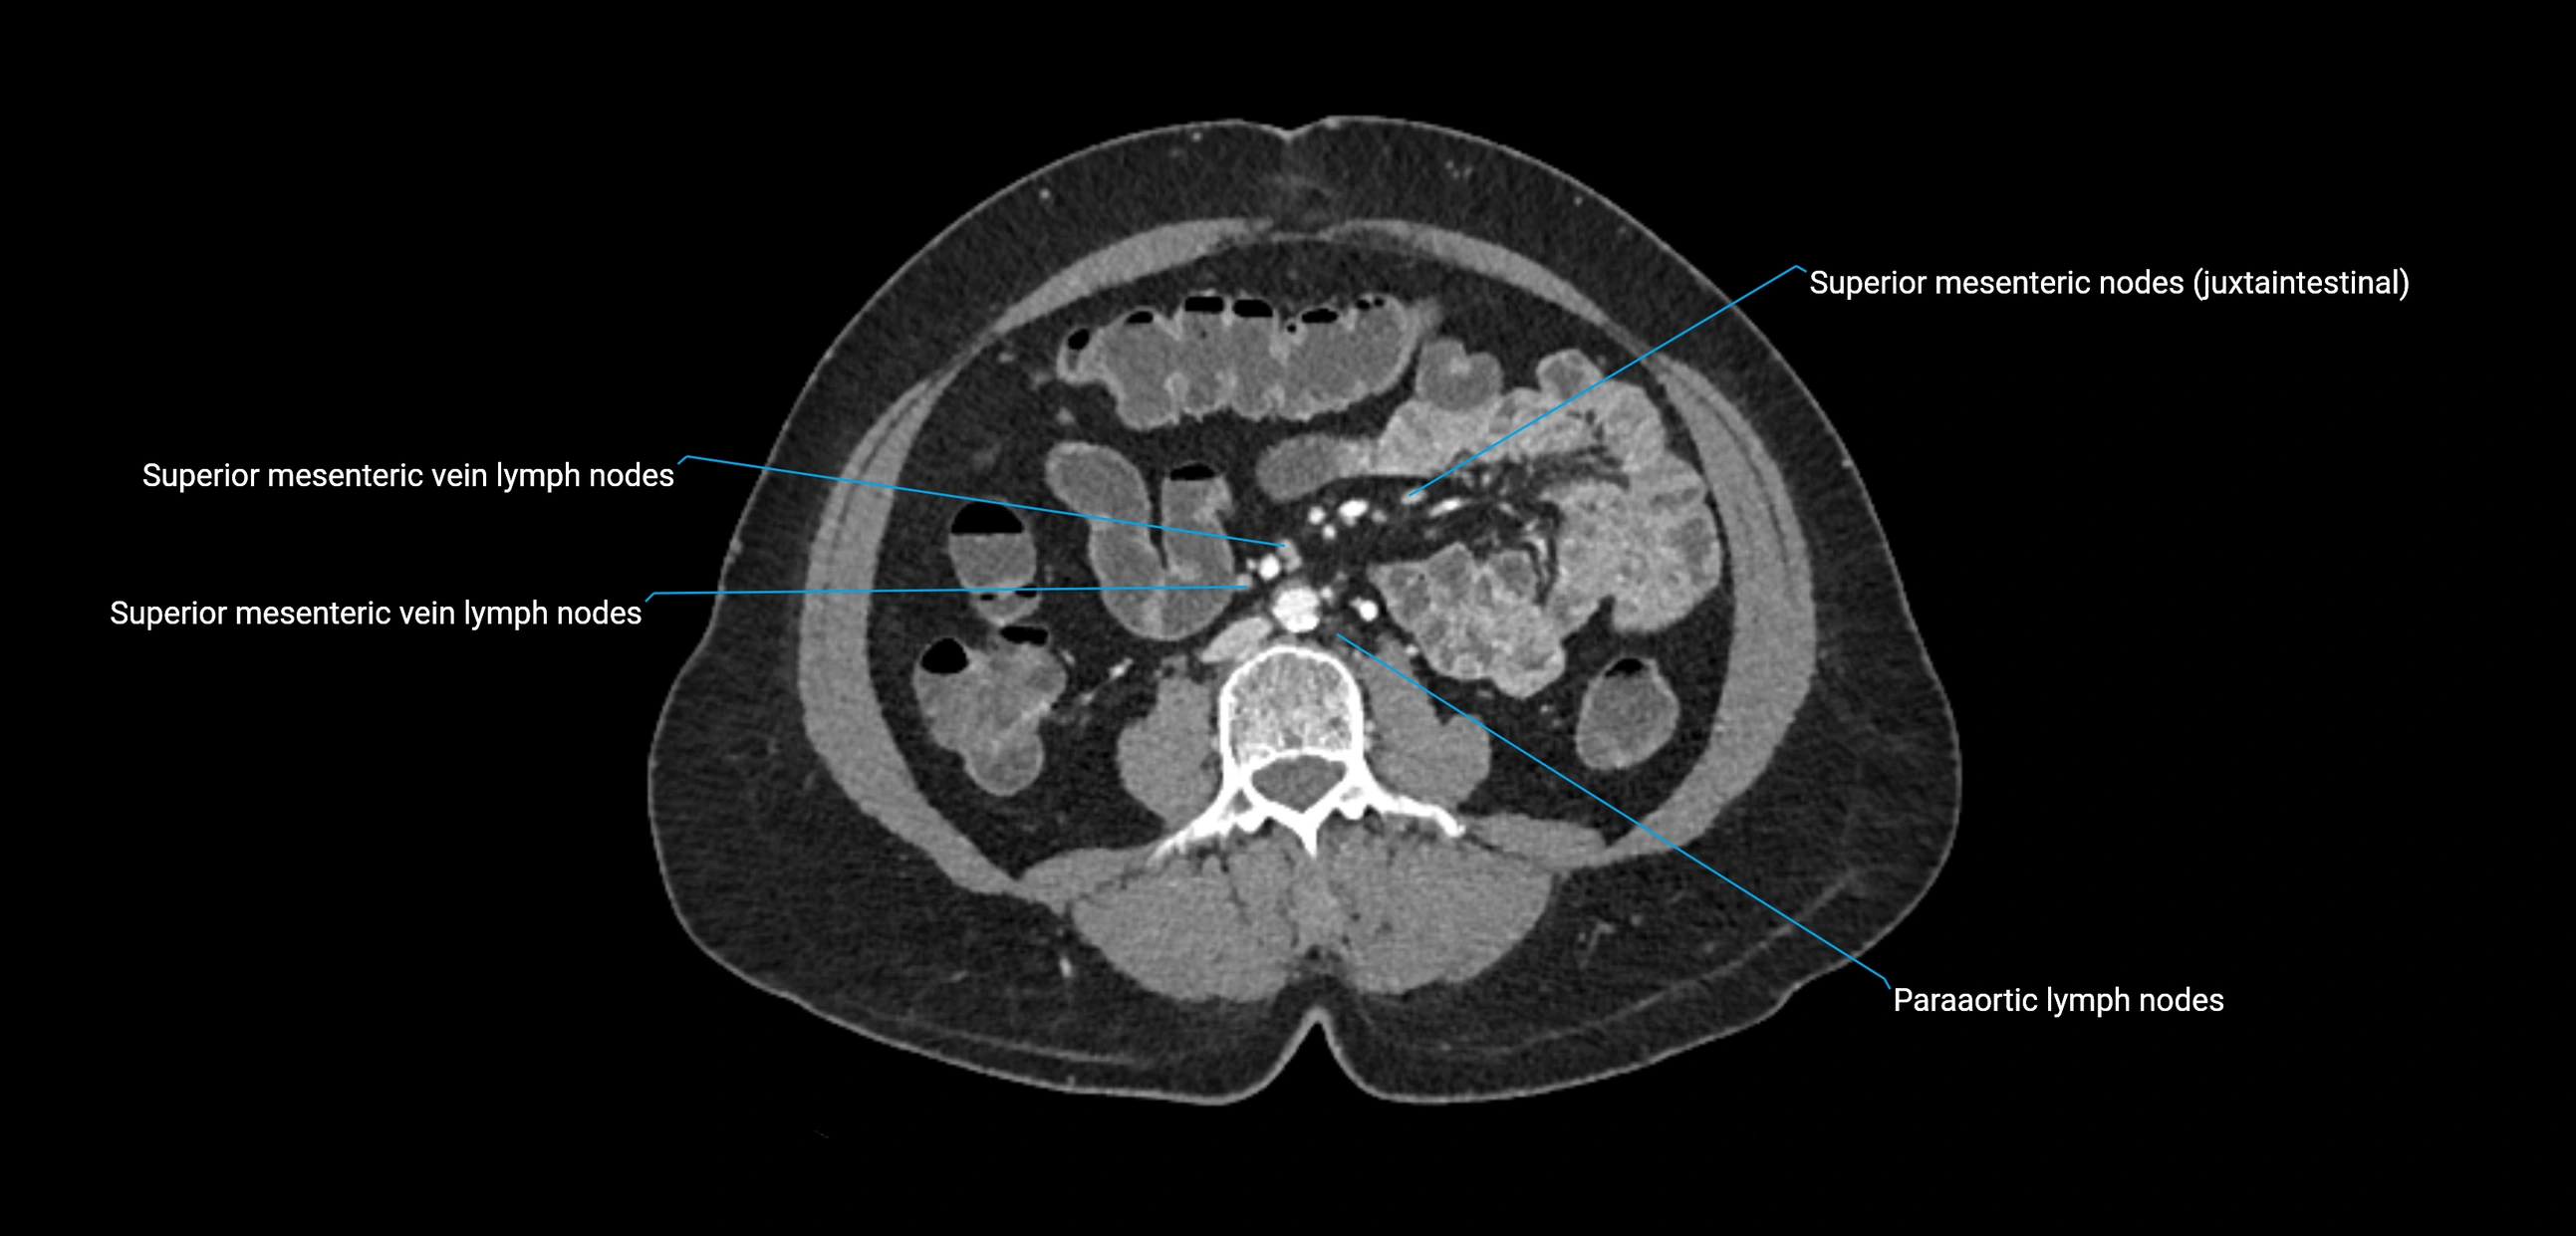

CT Appearance

CT Post-Contrast:

• Normal nodes enhance homogeneously

• Malignant nodes may show heterogeneous enhancement, central necrosis, or conglomerate formation

• Size >1 cm short axis is suspicious, though morphology and distribution are equally important

CT Venography (CTV):

• Demonstrates nodal encasement or compression of adjacent vessels (aorta, IVC, renal veins)

• Useful in staging testicular and ovarian malignancies

• Provides 3D reconstructions for retroperitoneal lymph node dissection planning